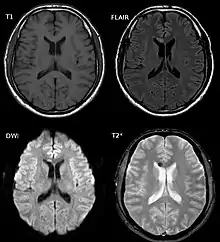

| Two MRI images of a patient with diffuse axonal injury resulting from trauma, at 1.5 tesla field strength. Left: conventional gradient recalled echo (GRE). Right: Susceptibility weighted image (SWI). | |